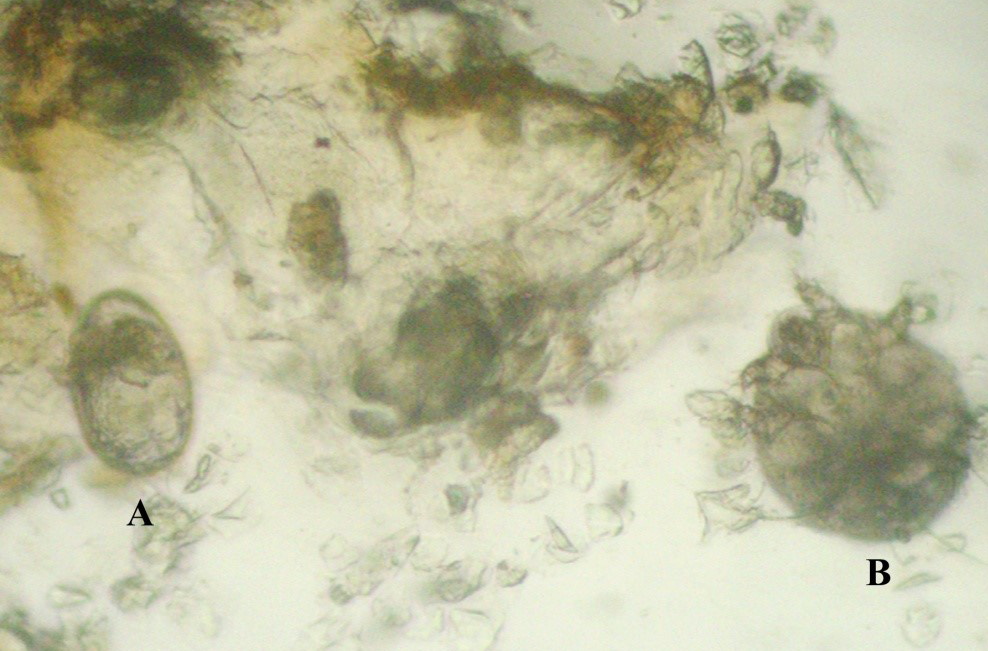

Figure 3

Otic discharges showing the Notoedres eggs (A) and adult mites (B) (400X)